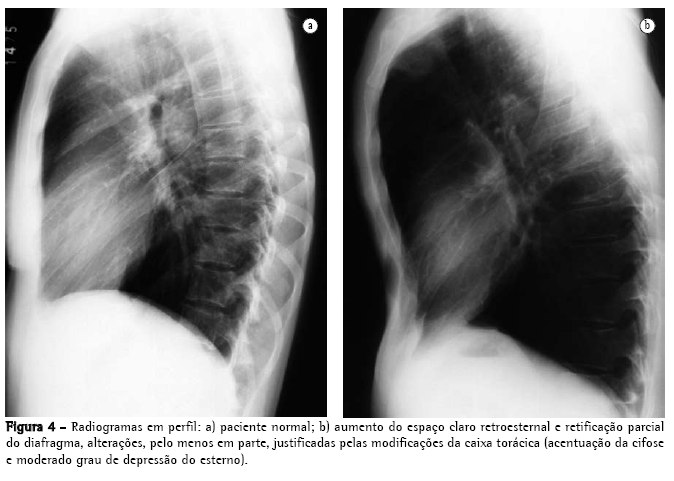

O rendimento do radiograma convencional de tórax na avaliação do enfisema é bastante limitado. Quando ainda não há aprisionamento aéreo significativo, a principal alteração é a redução da vasculatura, que somente é perceptível muito tardiamente na história natural da doença, e é um critério de extrema subjetividade. Quando há aprisionamento aéreo (Figuras 3 e 4), os critérios são mais seguros, podendo ser divididos em 3 grupos básicos de alterações,(6,8) apresentados na Quadro 1. Quando todos os critérios estão presentes, o diagnóstico é de certeza. Deve ser ressaltado que o aumento de câmaras direitas do coração, com redução da vasculatura intra-segmentar, pode também ser identificado em hipertensão arterial pulmonar, sem enfisema. Ressalta-se, também, que bolhas só estarão presentes em cerca de um terço dos casos.

Considerando-se que o hemidiafragma tem superfície de cerca de 250 cm2, pode-se calcular que cada 4 cm de deslocamento do diafragma determina deslocamento equivalente a cerca de 1 L de volume em cada pulmão (2 L, se considerados ambos os pulmões). Quando há aprisionamento de ar, a mobilidade do diafragma está limitada durante a expiração. O volume pulmonar no final da expiração é significativo no reconhecimento do enfisema. Normalmente, o deslocamento do diafragma entre a inspiração e a expiração máximas situa-se entre 3 e 10 cm, correspondendo a volumes de 1500 a 5000 mL. O deslocamento cranial menor que 2 ou 3 cm na expiração é indicativo de limitação da excursão diafragmática no indivíduo com enfisema.(21)

A utilização da altura do diafragma como um indicador diagnóstico é limitada em várias

situações:

nos pacientes com cifoescoliose;

em alguns indivíduos que apresentam diafragma em situação baixa na inspiração, porém preservam uma excelente mobilidade na expiração, como os atletas; e

em indivíduos com asma, especialmente crianças maiores e adolescentes, onde o diafragma pode apresentar algumas das características semelhantes às do diafragma do indivíduo com enfisema, porém as alterações cardiovasculares não estão presentes.

Nas três situações, a excursão diafragmática deve ser maior que a do indivíduo com enfisema.

A utilização da excursão diafragmática também tem limitações, especialmente em: pacientes com insuficiência cardíaca, onde as porções do diafragma que não estão em contato com o coração apresentam maior deslocamento cranial; e pacientes com edema pulmonar, pois a rigidez causada pelo edema pode determinar menor mobilidade do diafragma.